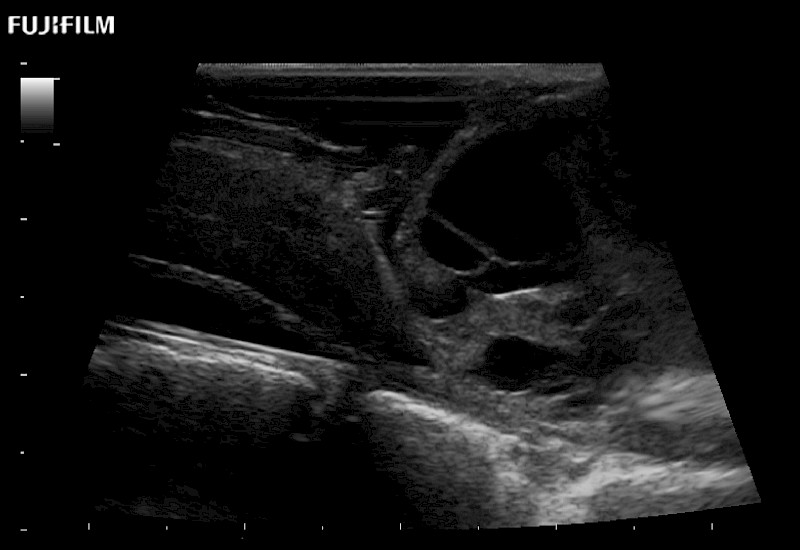

Exclusive 10mm side‐fire linear array transducer with 2.87mm diameter is ideal for real‐time visualization through and behind structures and instant, scalable definition of anatomy and vascularity including the ability to delineate and define tumor margins.

Main Specifications: